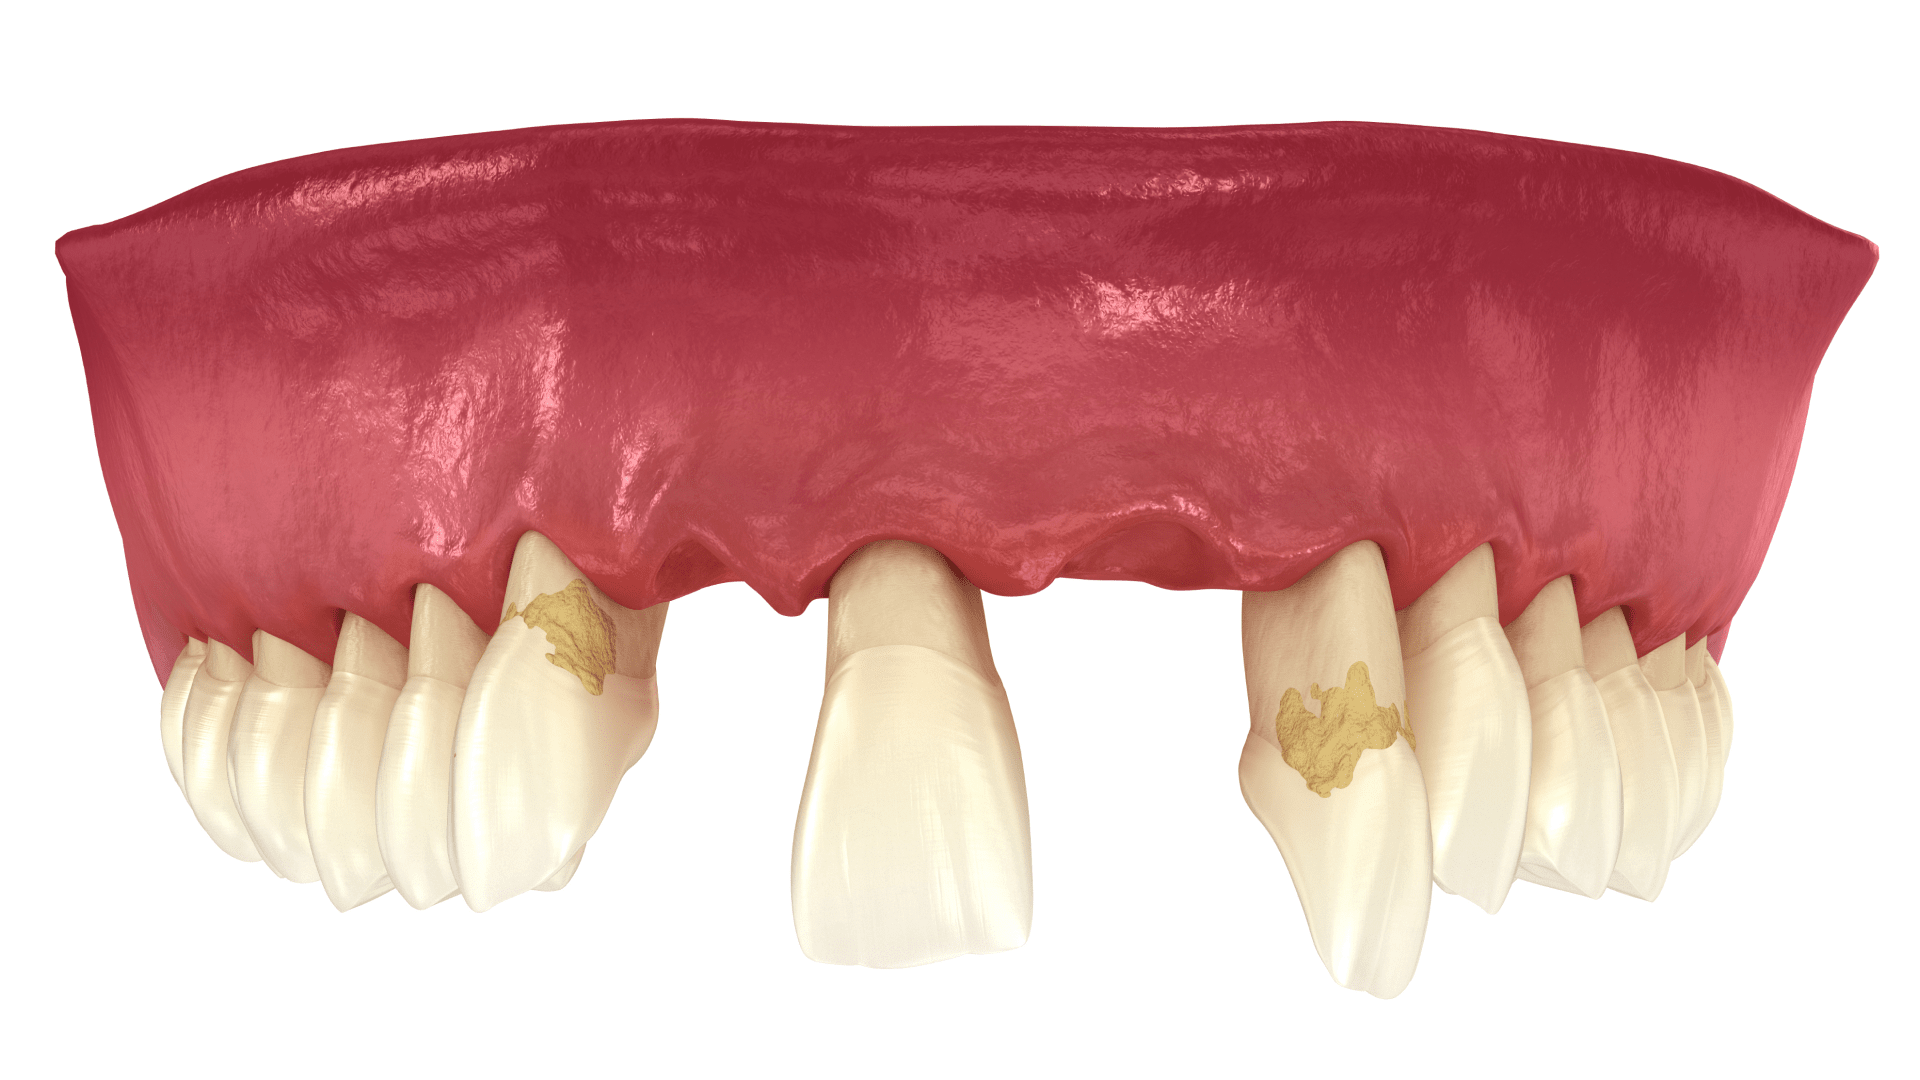

Імплантація зубів під час пародонтиту та пародонтозу

Захворювання пародонту найчастіше і стають причиною втрати зубів. З цього погляду пародонтит та пародонтоз є показаннями для проведення імплантації. До того ж потрібно враховувати, що активні інфекційно-запальні процеси потребують попереднього лікування. Тільки за таких умов надалі можливе відновлення зубного ряду.

Гнилі зуби – чи потрібно видаляти?

Різні частини зуба можуть руйнуватися під впливом різноманітних причин, насамперед карієсу. Врятувати зуб можна, якщо залишається здоровим корінь. Якщо ж процеси гниття почалися з кореня, зуб, зазвичай, видаляють.

Якщо пошкодилася коронкова частина зуба, ситуацію можна врятувати пломбуванням та іншими видами реставрації зубів. Стоматологи завжди радять своїм пацієнтам “не рубати з плеча” і постаратися врятувати природний зуб. Імплантацію та протези завжди можна встигнути зробити. Для початку потрібно зробити максимум для порятунку рідного зуба.